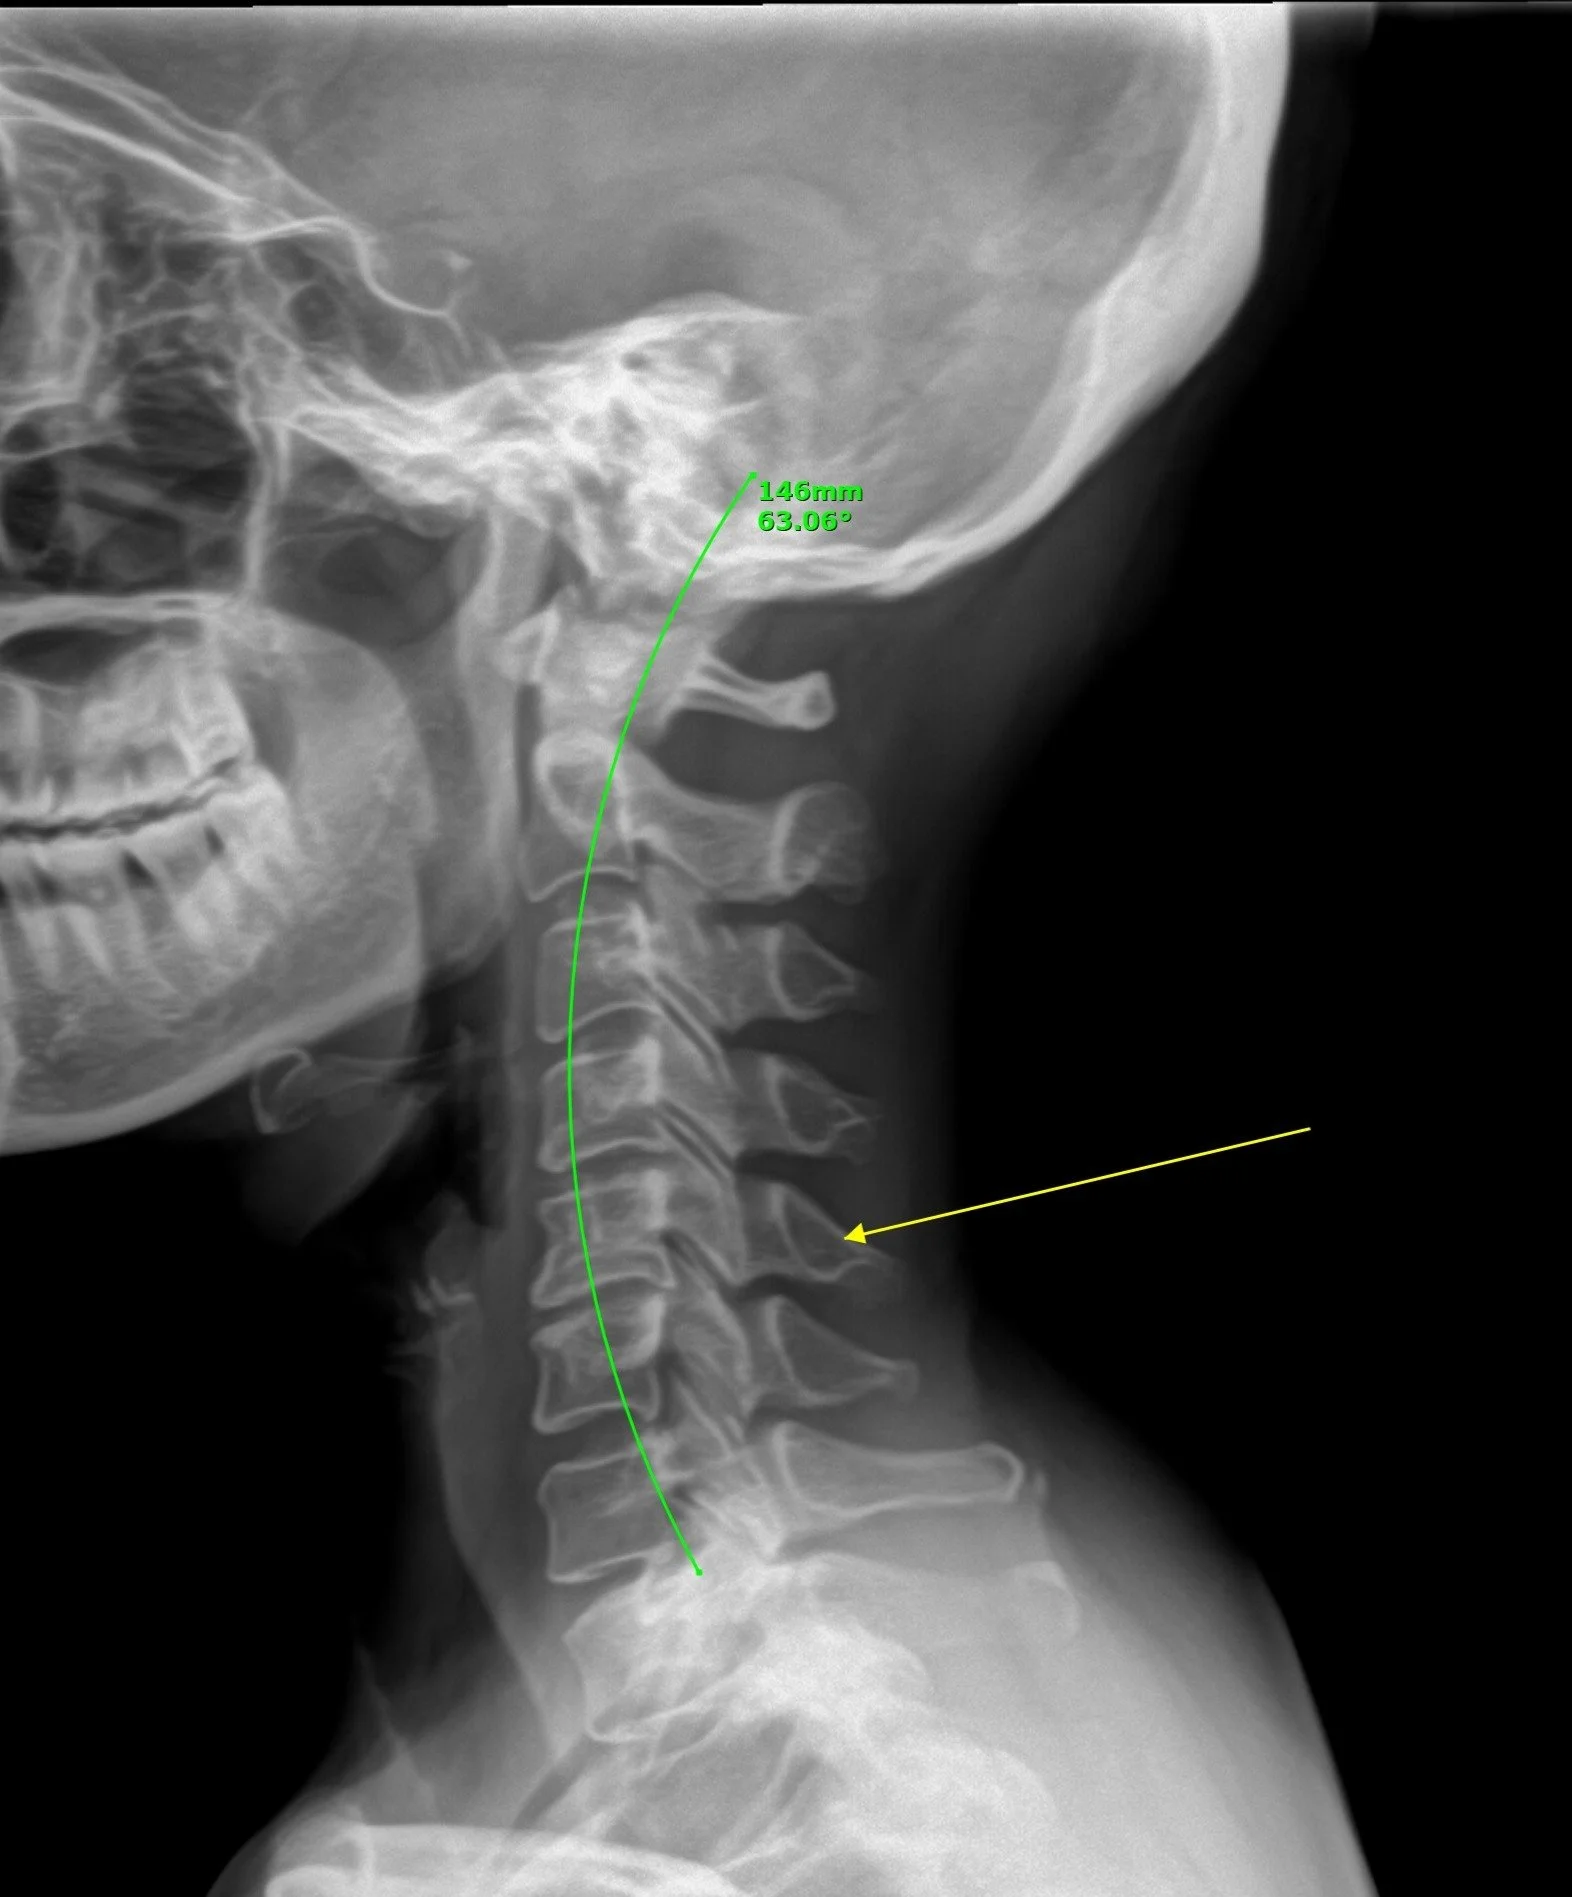

Digital X-rays

Digital plain spinal X-rays are diagnostic imaging tests that use a digital X-ray machine to create detailed images of the spine. These images can help doctors identify spinal conditions, such as fractures, arthritis, and spinal deformities.